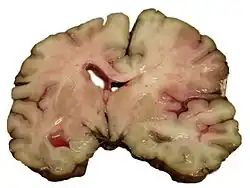

Ictus hemorrágico

Se deben a la rotura de un vaso sanguíneo encefálico debido a un pico hipertensivo o a un aneurisma congénito. Pueden clasificarse en: intraparenquimatosos y hemorragia subaracnoidea.

Las causas más frecuentes en la hemorragia cerebral son la hipertensión arterial y los aneurismas cerebrales.[32]

La hemorragia conduce a ictus a través de dos mecanismos. Por una parte, priva de riego al área cerebral dependiente de esa arteria, pero por otra parte, la sangre extravasada ejerce compresión sobre las estructuras cerebrales, incluidos otros vasos sanguíneos, lo que aumenta el área afectada. Ulteriormente, debido a las diferencias de presión osmótica, el hematoma producido atrae líquido plasmático, con lo que aumenta nuevamente el efecto compresivo local. Es por este mecanismo por lo que la valoración de la gravedad y el pronóstico médico de una hemorragia cerebral se demora 24 a 48 horas hasta la total definición del área afectada.